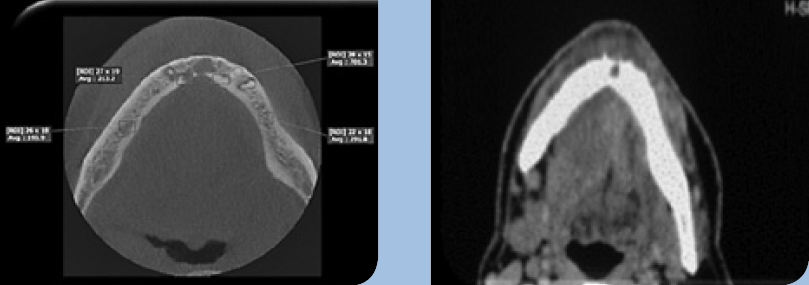

- Die Computertomographie (CT) ist nach wie vor das am häufigsten angewendete Verfahren. Die Vorteile liegen in einer guten Darstellung der Tumorläsion, des umgebenden Weichgewebes und der möglichen Knocheninfiltration. Andrle et al. konnten feststellen, dass die Computertomographie eine hohe Spezifität in der Erkennung von Knocheninfiltration aufweist (Quellenangabe). Ebenso weist die CT eine hohe Sensitivität in der Erkennung von besonders kleinen Arealen der Knocheninfiltration auf [7]. Nachteile der CT sind die geringere Auflösung, die hohe Strahlenbelastung sowie die ausgeprägten Metallartefakte, wie z. B. bei metallischen Restaurationen.

- Die digitale Volumentomographie (DVT) liefert die höchste Auflösung von knöchernen Strukturen, die Darstellung und/oder Differenzierung von Weichgewebe ist jedoch nicht möglich. Vorteile sind die geringen Kosten und die im Vergleich zur CT reduzierten Metallartefakte. Nachteilig hingegen sind der geringe Weichteilkontrast und die Gewebedifferenzierung (Abb. 2 u. 3).

- Die Magnetresonanztomographie (MRT) liefert den besten Weichgewebekontrast. Dies macht sie besonders sensitiv in der Detektion von kleinen, im Frühstadium befindlichen Mundhöhlenkarzinomen. Die MRT weist eine hohe Spezifität und geringe Sensitivität in der Beurteilung der Knocheninfiltration auf. Vorteile sind die fehlende Strahlenbelastung sowie die geringe Ausprägung von Metallartefakten. Nachteile sind der Geräuschpegel, die lange Scandauer und die damit verbundene Gefahr von Bewegungsartefakten (Abb. 4 u. 5).